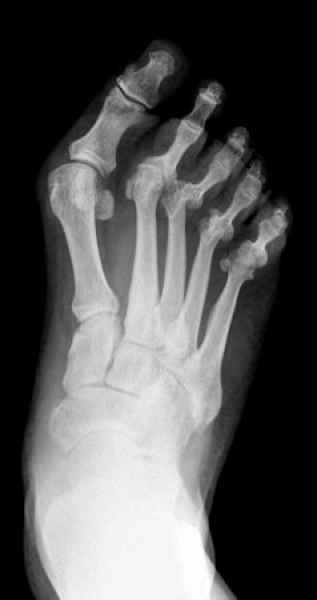

El pie es el órgano distintivo y característico de la especie humana, la única criatura que marcha erguida. El pie es una muy compleja estructura de arquitectura perfecta, adaptado a su función de apoyo, traslación, salto, con una riquísima sensibilidad que le permite detectar las más leves imperfecciones del suelo para estabilizar la marcha.

La marcha no solo es característica de la especie humana sino también de cada persona, y más aún varía según el estado de ánimo del momento. Una patología en los pies, se traduce en el rostro, en el ánimo, en el psiquismo. No sólo el dolor produce estos efectos, también un pie deformado o poco estético. En nuestra sociedad, la estética constituye un valor muy apreciado y estas alteraciones causan vergüenza fundamentalmente en las mujeres, que esconden en la playa sus pies en la arena y no pueden usar calzados elegantes.

Tanto la estructura del pie como su funcionalismo que es la marcha, pueden ser asiento y manifestación respectivamente de alteraciones locales ó sistémicas, por lo que su cuidadoso examen resulta de extrema utilidad diagnóstica.